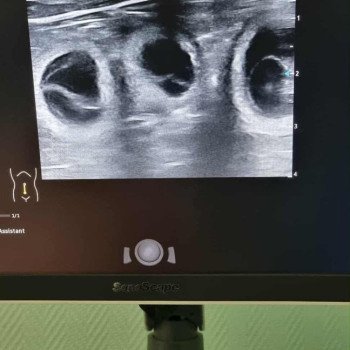

Vous retrouverez ici prochainement la nouvelle portée issue du mariage entre Suzy et Syrius